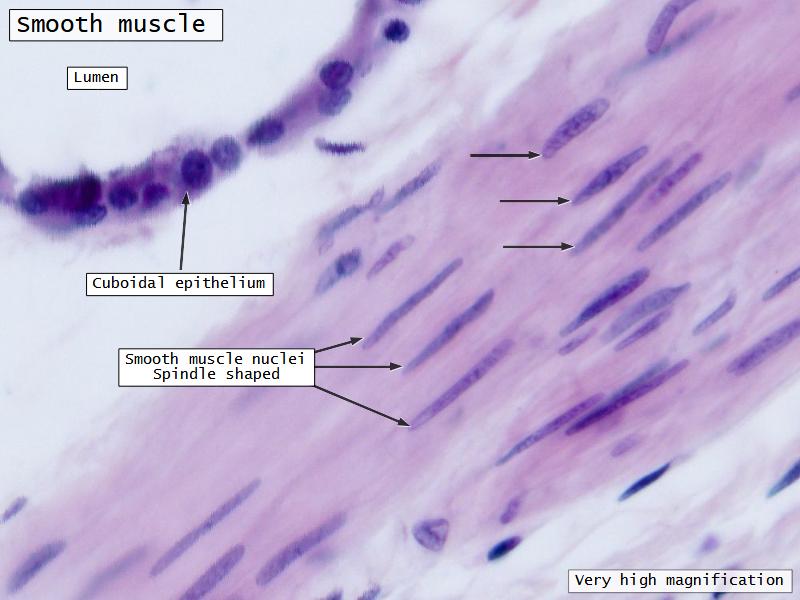

Nostril

Name three types of contractile cells.

- Smooth muscle REPLACE cartilage

- Ciliated columnar > Ciliated cuboidal

- Ciliated cuboidal epithelium

- Simple cuboidal epithelium